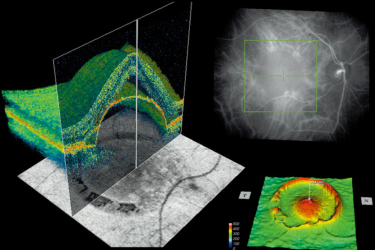

ОКТ (Оптическая когерентная томография) - это диагностическое обследование структур глаза, при котором используется лазер, сканирующий ткани глаза.

На обычном осмотре офтальмолога, к сожалению, невозможно детально изучить структуры глаза (диск зрительного нерва, сетчатка, роговица), а с помощью ОКТ, мы не только получаем детальное изображение в виде срезов, а так же можем увидеть показатели толщины, объема и т.д. в числах.